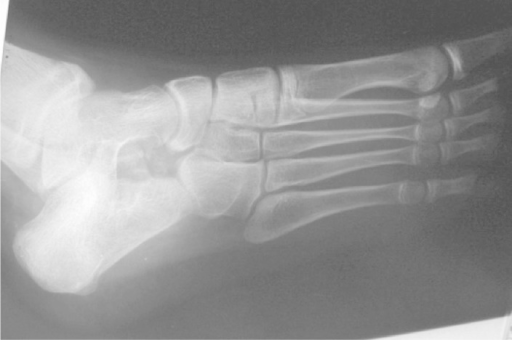

Lateral weight-bearing radiograph of an adolescent foot demonstrating features of talocalcaneal coalition. There is a positive C-sign (continuous arc from dome of talus to sustentaculum tali). Talar beaking is visible (dorsal spurring of talar head). The subtalar joint appears indistinct. The hindfoot is in valgus. CT is recommended to characterize the coalition (fibrous, cartilaginous, or osseous) and determine resectability.

Source: Talocalcaneal Coalition Lateral Radiograph • PMC4799062 • CC-BY